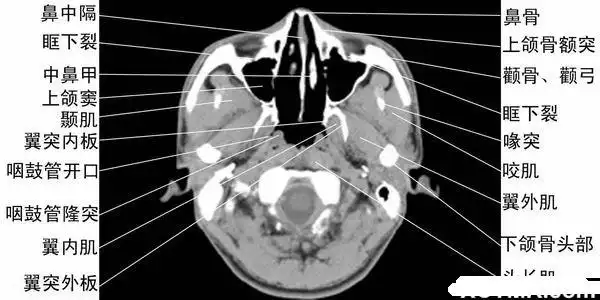

鼻及鼻窦的影像诊断

ct轴位鼻腔和鼻窦层面(解剖图片)